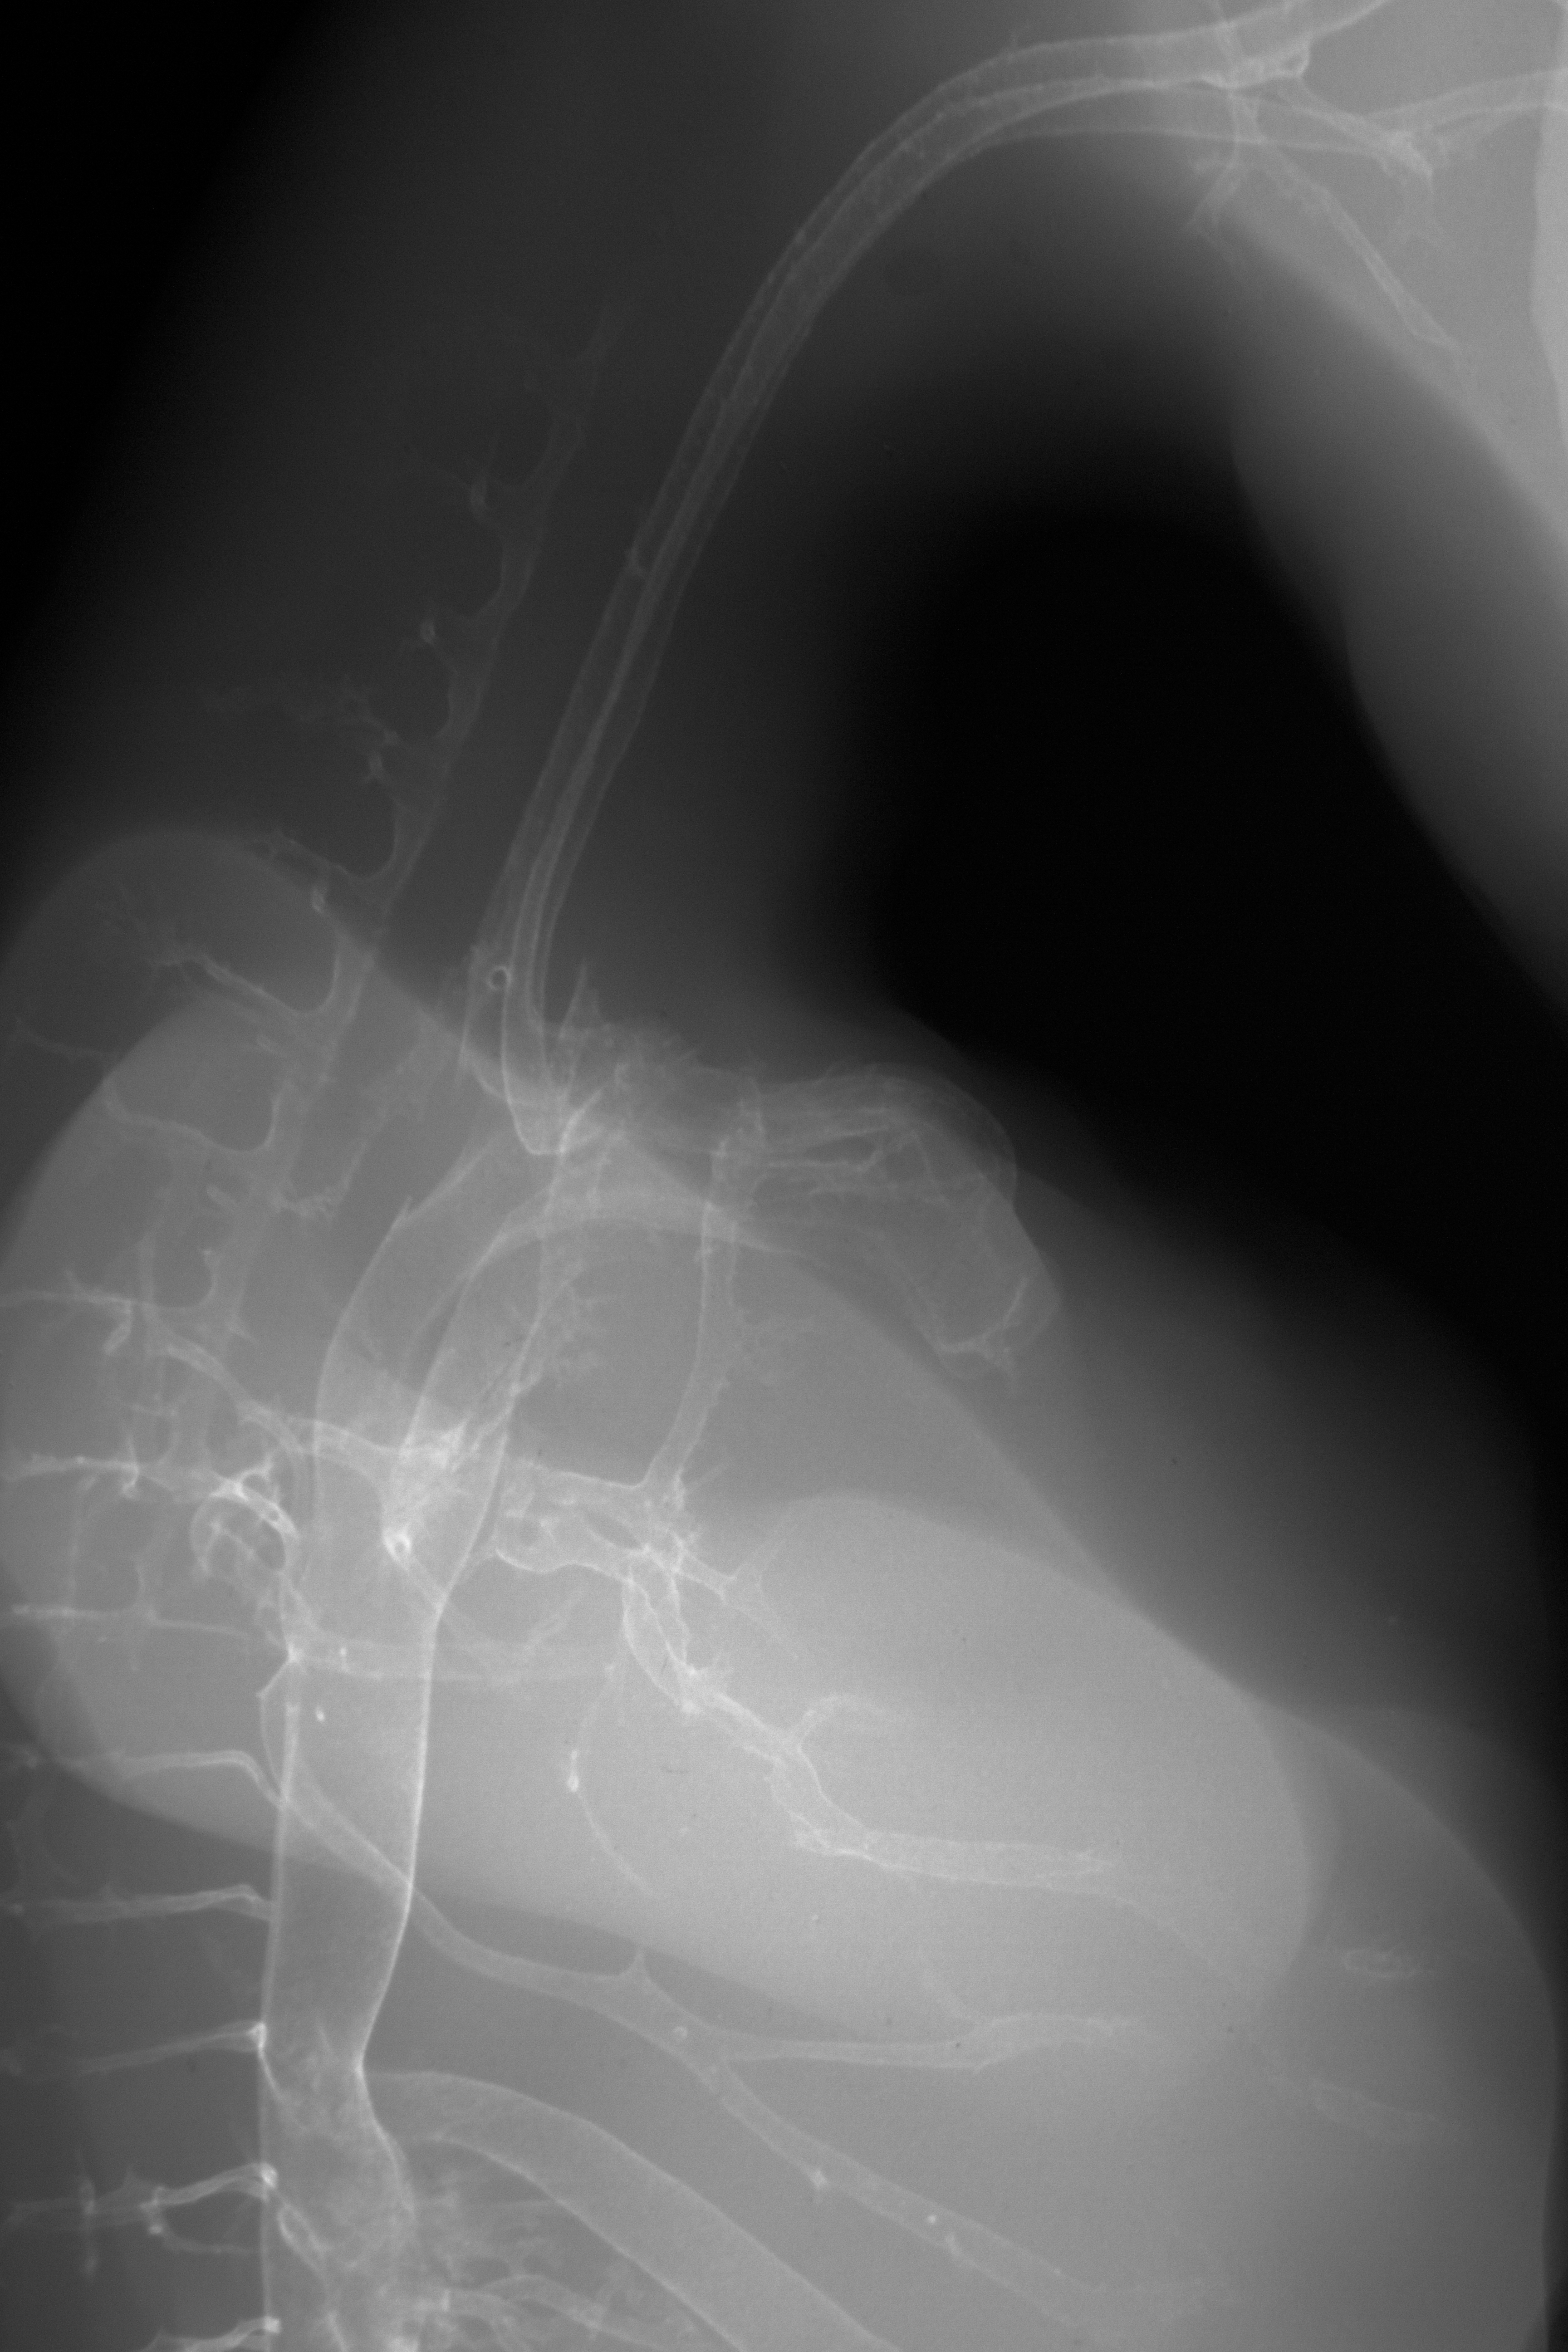

Chick Embryo Microangiography

Hamburger-Hamilton (HH) Stage 30 (approx. 6.5 days)

X-Ray Micrographs